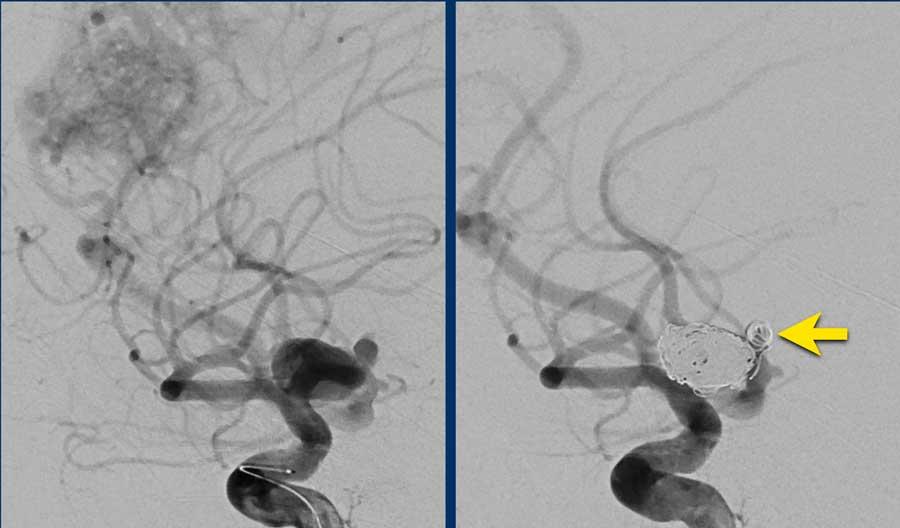

Hình bên trái: DSA túi phình trước điều trị.

Hình bên phải: DSA sau điều trị bằng đặt coil riêng biệt cho túi phình chính và túi phình con (mũi tên vàng).

Quyết định điều trị túi phình trước và phẫu thuật cắt bỏ AVM trong giai đoạn bán cấp khi bệnh nhân đã hồi phục sau xuất huyết dưới nhện.